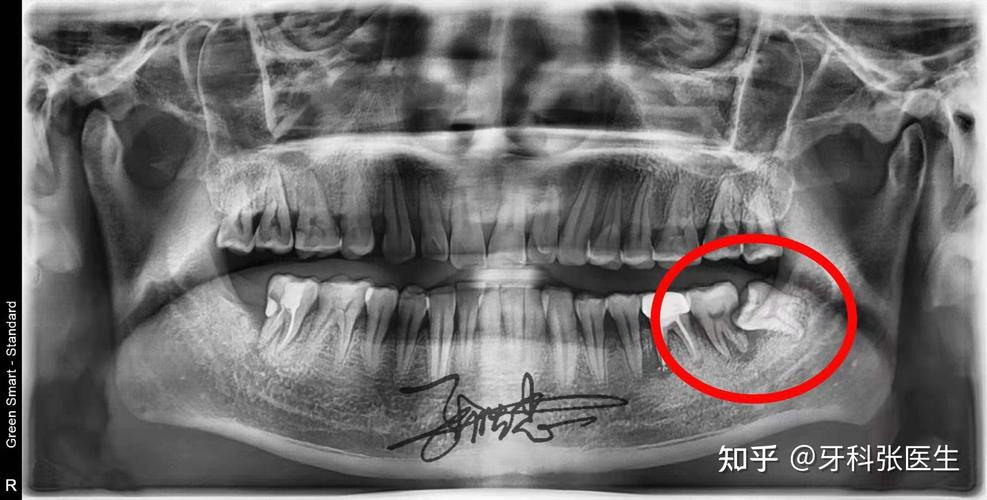

哭哭,我的智齿太靠近神经管了怎么办

智齿紧贴神经该怎么办上篇

下颌智齿离下牙槽神经管越近,难度也越大.

拔智齿伤神经吗?